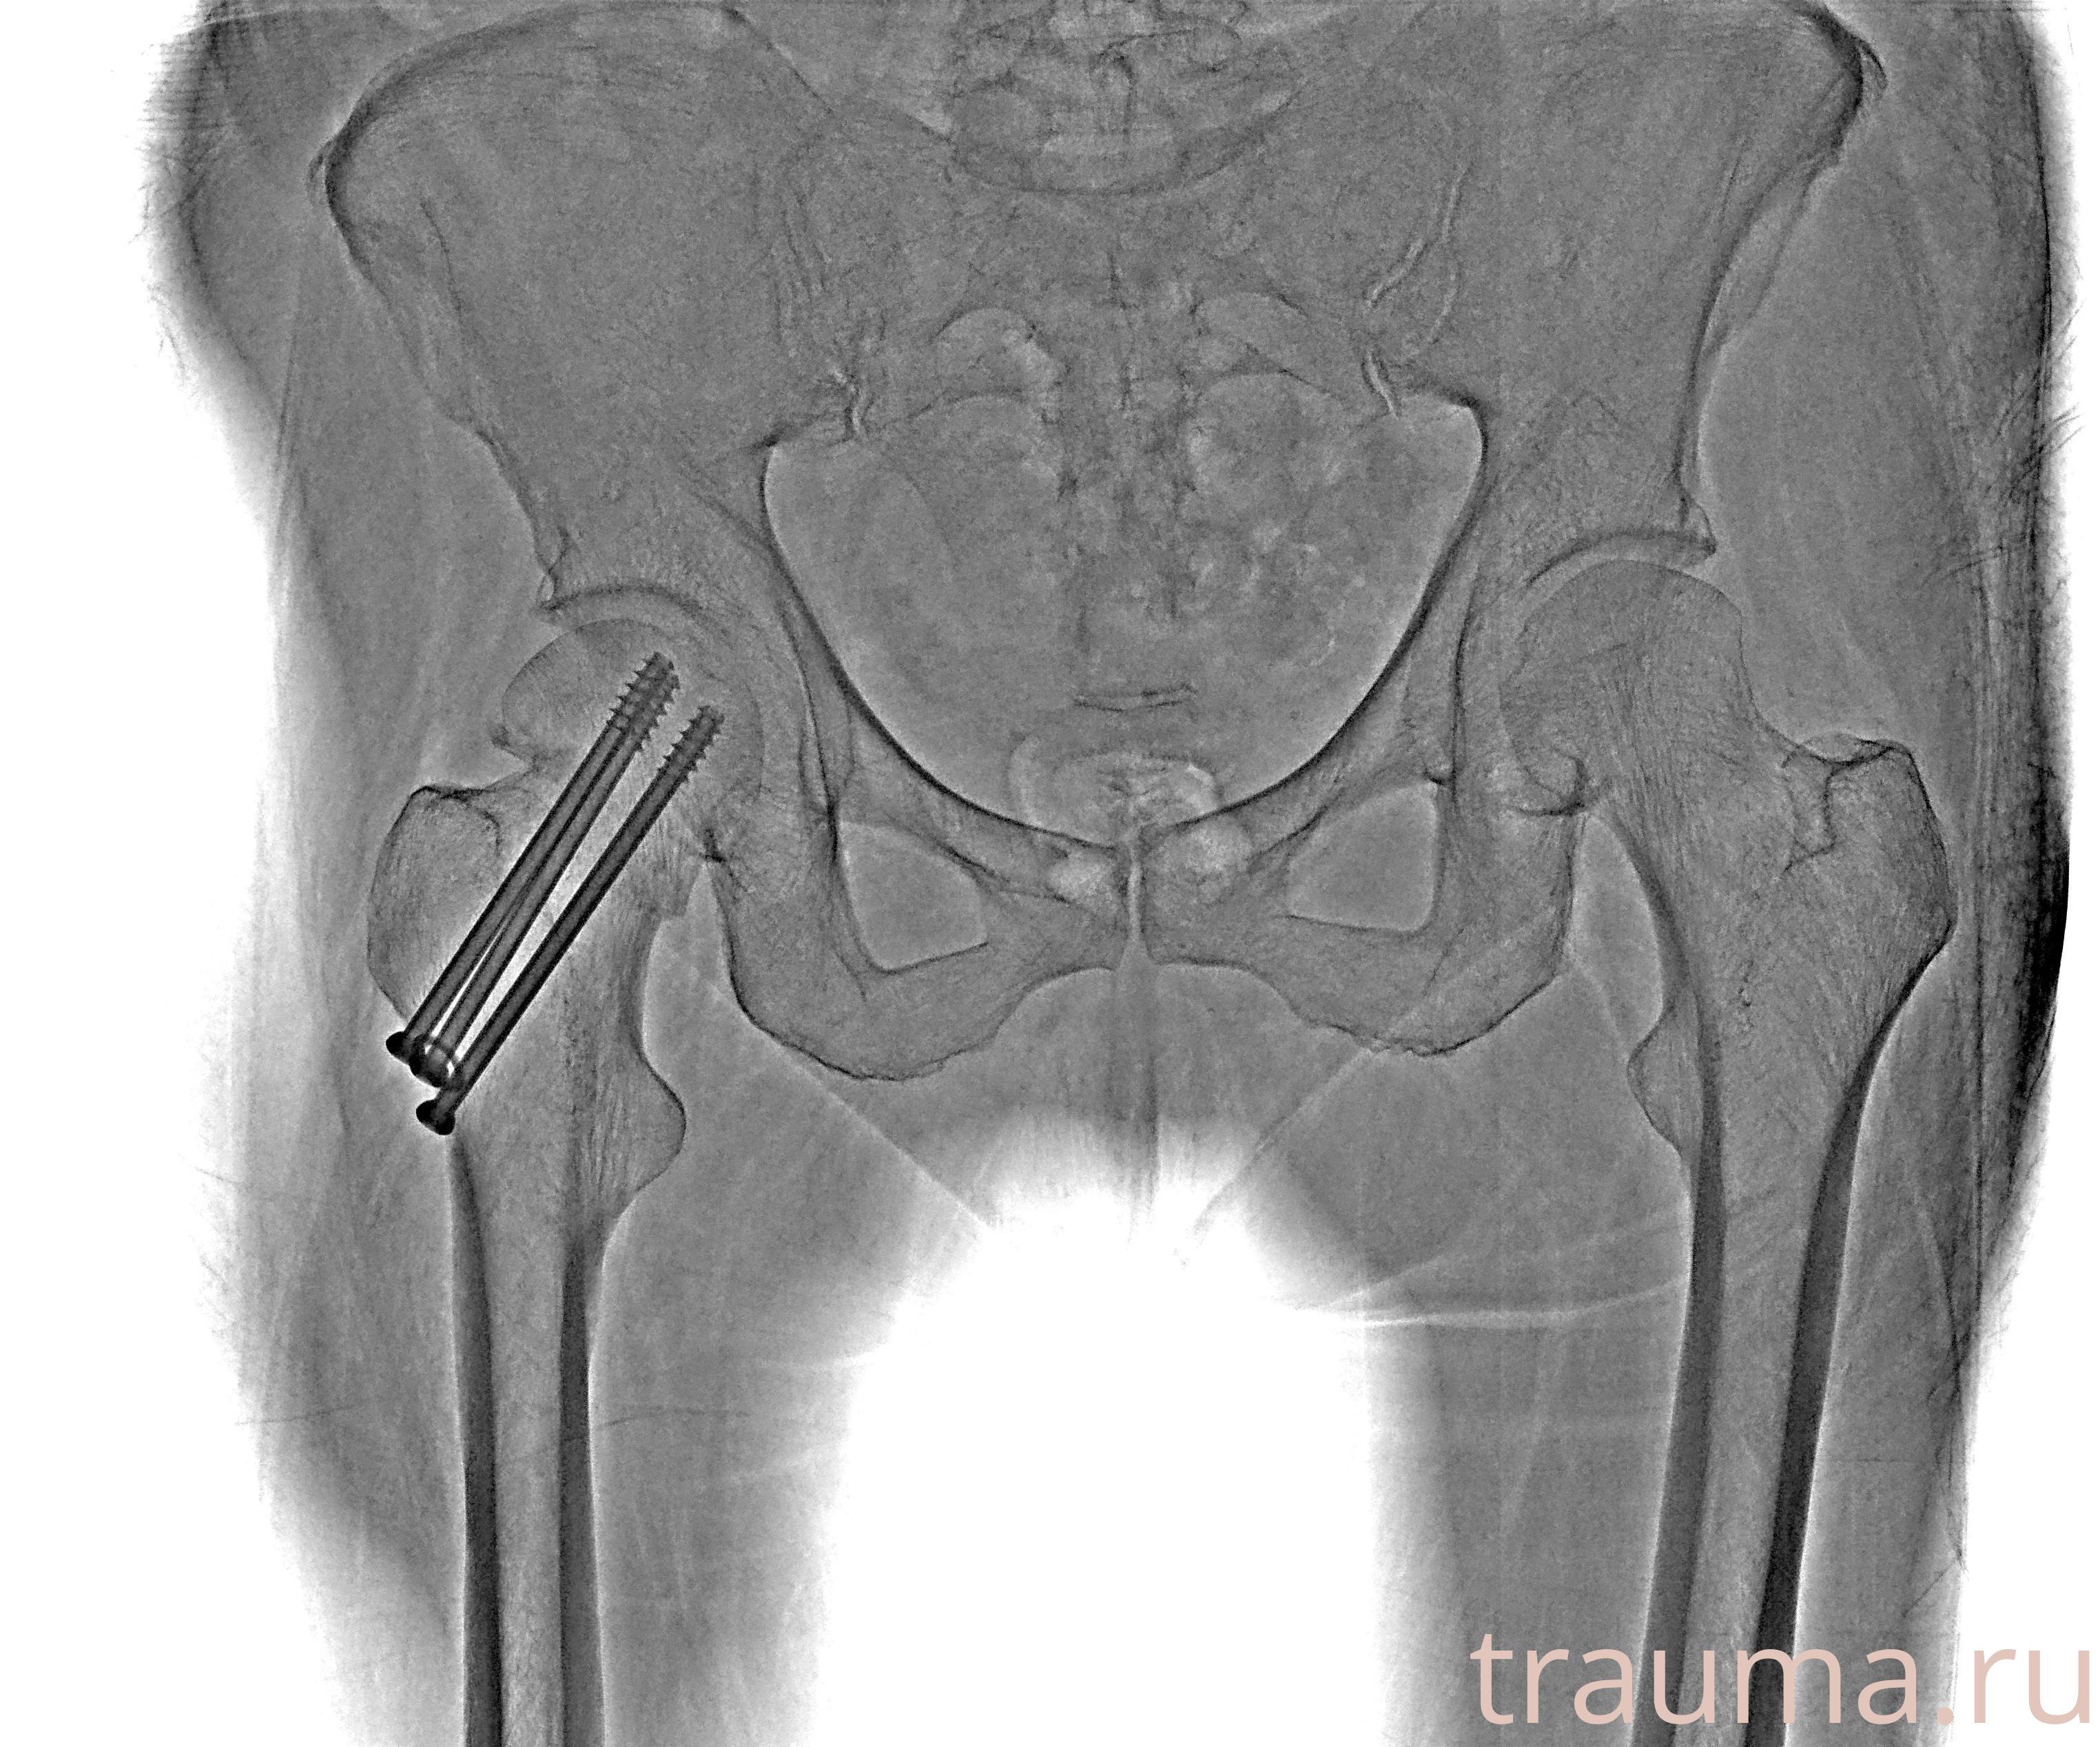

Рентгенограммы